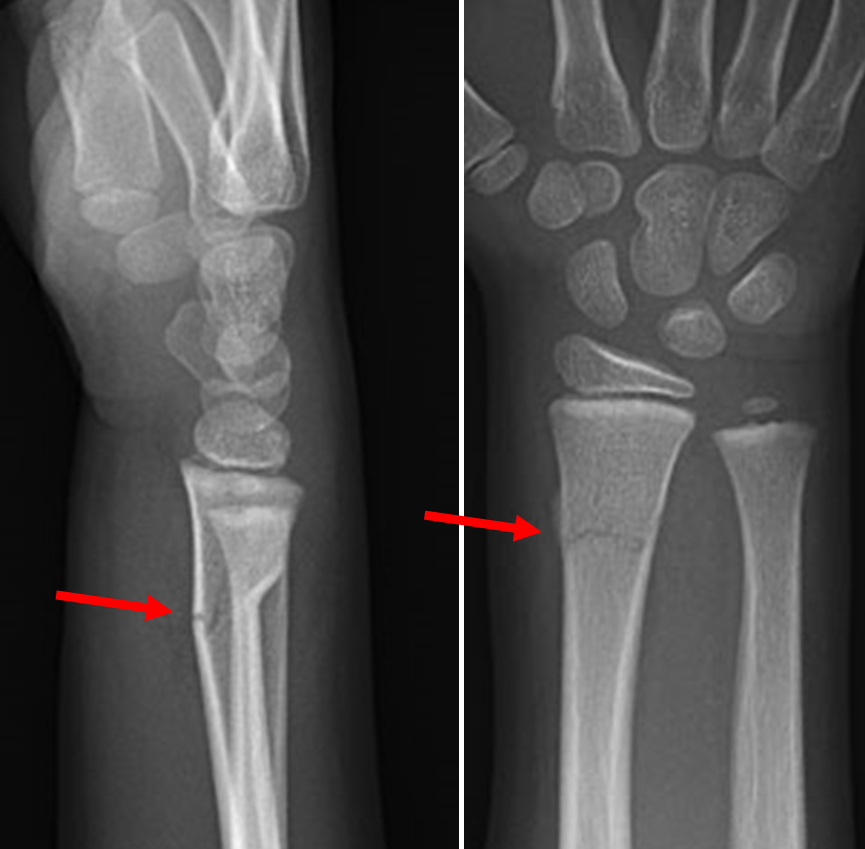

Example xray of distal radius buckle fracture:

Case courtesy of Dr Maulik S Patel, Radiopaedia.org. From the case rID: 10733